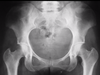

Diagnosis?

Cause?

Particle disease (aka aggressive granulomatosis).

An osteolytic histiocytic response of the bone to small polyethylene particles shed from the articular lining of orthopedic hardware. Look for abnormal liner wear, evident by superiorly malpositioned femoral head component in this case. May be asymptomatic until it is enough to cause loosening.